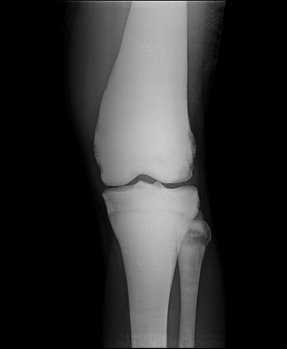

Остеопетроз описывается как синдром чрезмерной кальцификации костей, вызывающий мраморный вид с повышенной рентгенологической плотностью скелета (рис. 1, 2, 3).

Рис. 2. Рентгенограмма костей бедра и голени при мраморной болезни

Рентгеновская картина мраморной болезни очень своеобразна. Больше всего поражается основание черепа, позвонки, ребра, проксимальные концы бедренных костей и дистальные берцовых костей. Menee изменены плечевые кости и фаланги. Эпифизы несколько утолщены. Метафизы более всего изменены и имеют булавовидную форму. Кости — плотны и непрозрачны. Костномозговой канал виден резко суженным. Иногда на фоне плотной мраморной кости имеются широкие поперечные светлые полосы нормального строения кости (С.

Свое название мраморная болезнь получила в связи с особой картиной рентгенограмм скелета, на которых обнаруживают необычно резкую плотность, гомогенность, бесструктурность костей, как будто они состоят из белого мрамора. Форма и размеры костей остаются нормальными. В костях черепа в первую очередь поражаются те, которые имеют хрящевое происхождение. Вместе со склерозом костной ткани отмечается сужение каналов черепных нервов, облитерируются придаточные пазухи носа. В теле позвонков центральная часть просветлена, а по ходу замыкающих пластинок образуются плотные широкие полосы.

Рентгенологическая картина характеризуется диффузным тотальным уплотнением костей со специфическими изменениями позвонков, костей таза и метафизарных областей. Лабораторно - отмечается снижение уровня кальция и повышение уровня фосфора сыворотки крови.

Синонимы: мраморная болезнь, семейный остеопороз, врожденный диффузный остеосклероз. Диффузный остеосклероз или остеопороз значительной части костного скелета. Патогенез не выяснен. У половины больных клинических симптомов нет, болезнь диагностируют случайно при рентгенологическом исследовании по поводу перелома. Это заболевание доброкачественное, наследуется доминантно. Пораженные кости отличаются большой ломкостью. Сущность патологических изменений заключается в утолщении коркового слоя костей и сужении костномозгового канала, прогрессирующем остеосклерозе, уплотнении с одновременной хрупкостью костей и анемией. Наиболее выражены изменения в зонах роста, где бывают, видны колбовидные вздутия. В костях черепа суживаются отверстия со сдавленней нервов, из-за чего наступает глухота и слепота. Смерть может наступить при явлениях нарастающей анемии или от септикопиемии, источником которой являются гнойные остеомиелиты, развивающиеся как следствие патологических переломов. Когда в процесс вовлекается миелогенная ткань, заболевание принимает злокачественный (по течению) характер, проявляющийся в грудном возрасте задержкой роста, спонтанными переломами, значительной анемией, увеличением печени и селезенки, слепотой, тяжелым остеомиелитом. Тип наследования аутосомно-рецессивный. Прогноз неблагоприятен. Смерть в раннем возрасте из-за недостаточности костного мозга и геморрагического синдрома. На рентгенограммах пораженные кости имеют бесструктурное, как бы мраморное изображение, костномозговые пространства сужены, остеосклероз выражен в области длинных трубчатых костей, позвонков, таза.